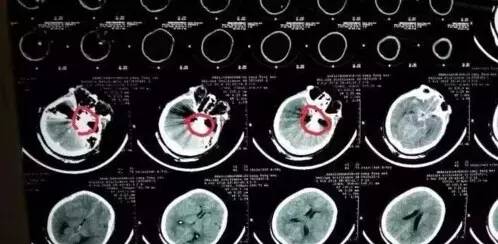

这名女子左侧面部被炸出了一个骇人的大“窟窿”,舌咽外露,胸部、腹部多处皮肤裂伤,左手也被炸得血肉模糊,陷入昏迷状态。医生表示,该患者生命垂危,已休克。由于大量出血,该女子血色素仅为正常值的1/3。患者头部CT显示,颅内有多处异物,且深达颅底及脑干,伤及颅内最大动脉,蛛网膜下腔出血。